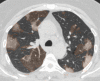

The coronavirus disease 2019 (COVID-19) pandemic is a global health care emergency. Although reverse-transcription polymerase chain reaction testing is the reference standard method to identify patients with COVID-19 infection, chest radiography and CT play a vital role in the detection and management of these patients. Prediction models for COVID-19 imaging are rapidly being developed to support medical decision making. However, inadequate availability of a diverse annotated data set has limited the performance and generalizability of existing models. To address this unmet need, the RSNA and Society of Thoracic Radiology collaborated to develop the RSNA International COVID-19 Open Radiology Database (RICORD). This database is the first multi-institutional, multinational, expert-annotated COVID-19 imaging data set. It is made freely available to the machine learning community as a research and educational resource for COVID-19 chest imaging. Pixel-level volumetric segmentation with clinical annotations was performed by thoracic radiology subspecialists for all COVID-19-positive thoracic CT scans. The labeling schema was coordinated with other international consensus panels and COVID-19 data annotation efforts, the European Society of Medical Imaging Informatics, the American College of Radiology, and the American Association of Physicists in Medicine. Study-level COVID-19 classification labels for chest radiographs were annotated by three radiologists, with majority vote adjudication by board-certified radiologists. RICORD consists of 240 thoracic CT scans and 1000 chest radiographs contributed from four international sites. It is anticipated that RICORD will ideally lead to prediction models that can demonstrate sustained performance across populations and health care systems.